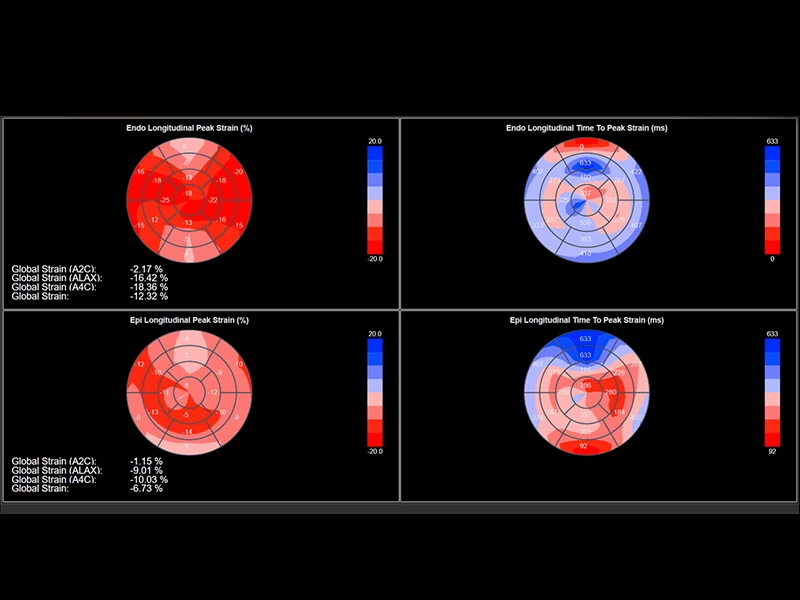

MyLab™Sigma - Left Ventricle XStrain 2D analysis

MyLab™Sigma - Left Ventricle XStrain 2D analysis